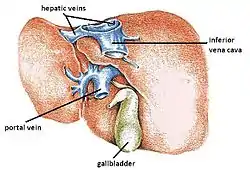

The hepatic veins are the veins that drain de-oxygenated blood from the liver into the inferior vena cava. There are usually three upper hepatic veins draining from the left, middle, and right parts of the liver. These are larger than the group of lower hepatic veins that can number from six to twenty. All of the hepatic veins drain into the inferior vena cava.[1]

The hepatic veins are the veins of the liver, two of which are shown in this diagram. | |

They are one of two sets of veins connected to the liver, the others are the portal veins.